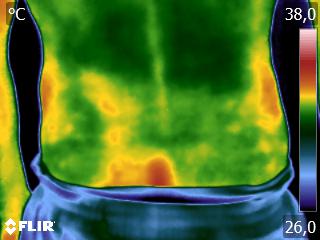

Como no caso da sequência de termogramas abaixo de uma paciente do sexo feminino, 42 anos, sem comorbidade e que apresentou dor em joelhos após treino de musculação. Foi realizado uma Análise Termofuncional e detectado alterações térmicas condizentes com o relato de dor.

Estas informações foram a oportunidade para convencer a paciente a realizar uma ressonância magnética para determinar o grau de comprometimento tecidual. Pois sem isso, após a melhora da dor, a liberação de carga e até a carga terapêutica ficariam limitadas.

Já com este conhecimento foi possível determinar um tratamento que abarcasse as áreas de dor e as áreas de comprometimento tecidual que apresentam inflamação, até a paciente retornar com o resultado da ressonância.

Isso adianta e muito a reabilitação, pois oferece informação que a olho nu não seria possível.